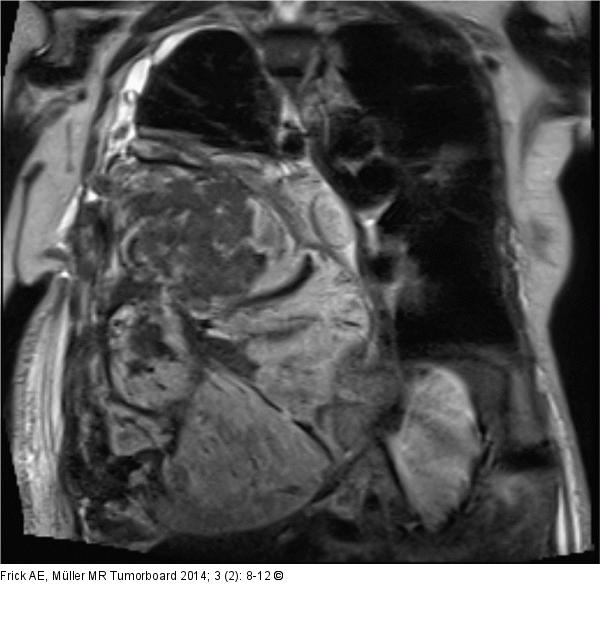

Abbildung 3: Biphasisches Synovialsarkom Koronare Schnittbildgebung mittels MRT mit KM 1,5 Tesla T1- und T2-gewichtet: Großer rechtsthorakaler Tumor mit Einwachsen des Tumors in das Diaphragma und einem Tumorzapfen in den rechten Leberlappen (Infiltration?). Ein direkter Kontakt zur 11. Rippe rechts ist sichtbar, wobei diese Region in der MRT hyperintens signalalteriert ist, im Sinne einer Knocheninfiltration. Deutliches Mediastinal- Shifting nach links. |

Abbildung 3: Biphasisches Synovialsarkom

Koronare Schnittbildgebung mittels MRT mit KM 1,5 Tesla T1- und T2-gewichtet: Großer rechtsthorakaler Tumor mit Einwachsen des Tumors in das Diaphragma und einem Tumorzapfen in den rechten Leberlappen (Infiltration?). Ein direkter Kontakt zur 11. Rippe rechts ist sichtbar, wobei diese Region in der MRT hyperintens signalalteriert ist, im Sinne einer Knocheninfiltration. Deutliches Mediastinal- Shifting nach links. |